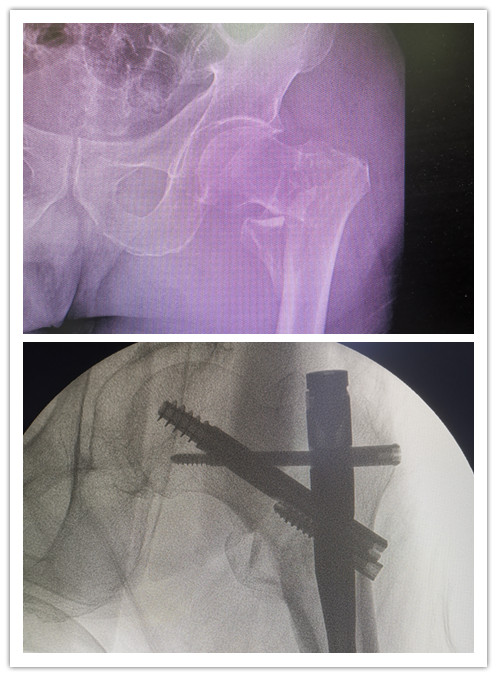

前不久,89歲的廖老因?yàn)樽呗窌r(shí)不小心摔傷左髖部,被緊急送到石化醫(yī)院。X線檢查顯示,廖老的左股骨轉(zhuǎn)子間粉碎性骨折。在完善相關(guān)輔助檢查后,骨科副主任醫(yī)師楊琲、錢立標(biāo)帶領(lǐng)團(tuán)隊(duì)認(rèn)真研究患者影像資料,考慮其基礎(chǔ)疾病較多,有高血壓、糖尿病以及重度骨質(zhì)疏松癥病史,再結(jié)合年齡、病情和康復(fù)鍛煉需要,召集多學(xué)科綜合會(huì)診評(píng)估風(fēng)險(xiǎn)。經(jīng)與患者和家屬積極溝通,最終決定運(yùn)用股骨髓內(nèi)釘系統(tǒng)PFBN,為廖老行股骨轉(zhuǎn)子間骨折閉合復(fù)位內(nèi)固定手術(shù)。

手術(shù)當(dāng)日,在麻醉科的協(xié)助下,骨科團(tuán)隊(duì)經(jīng)透視成功將廖老的左髖部牽引復(fù)位,用4個(gè)小切口順利置入PFBN固定,不到40分鐘就成功完成手術(shù)。